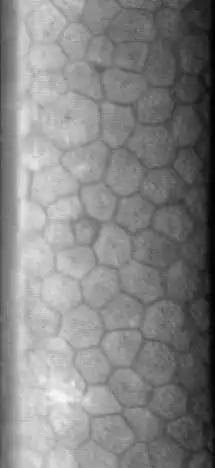

The normal corneal endothelium is a single layer of uniformly sized cells with a predominantly hexagonal shape. This honeycomb tiling scheme yields the greatest efficiency, in terms of total perimeter, of packing the posterior corneal surface with cells of a given area. The corneal endothelium is attached to the rest of the cornea through Descemet's membrane, which is an acellular layer composed mostly of collagen IV.

Hexagonal cells of corneal endothelium visualized by specular microscopy.